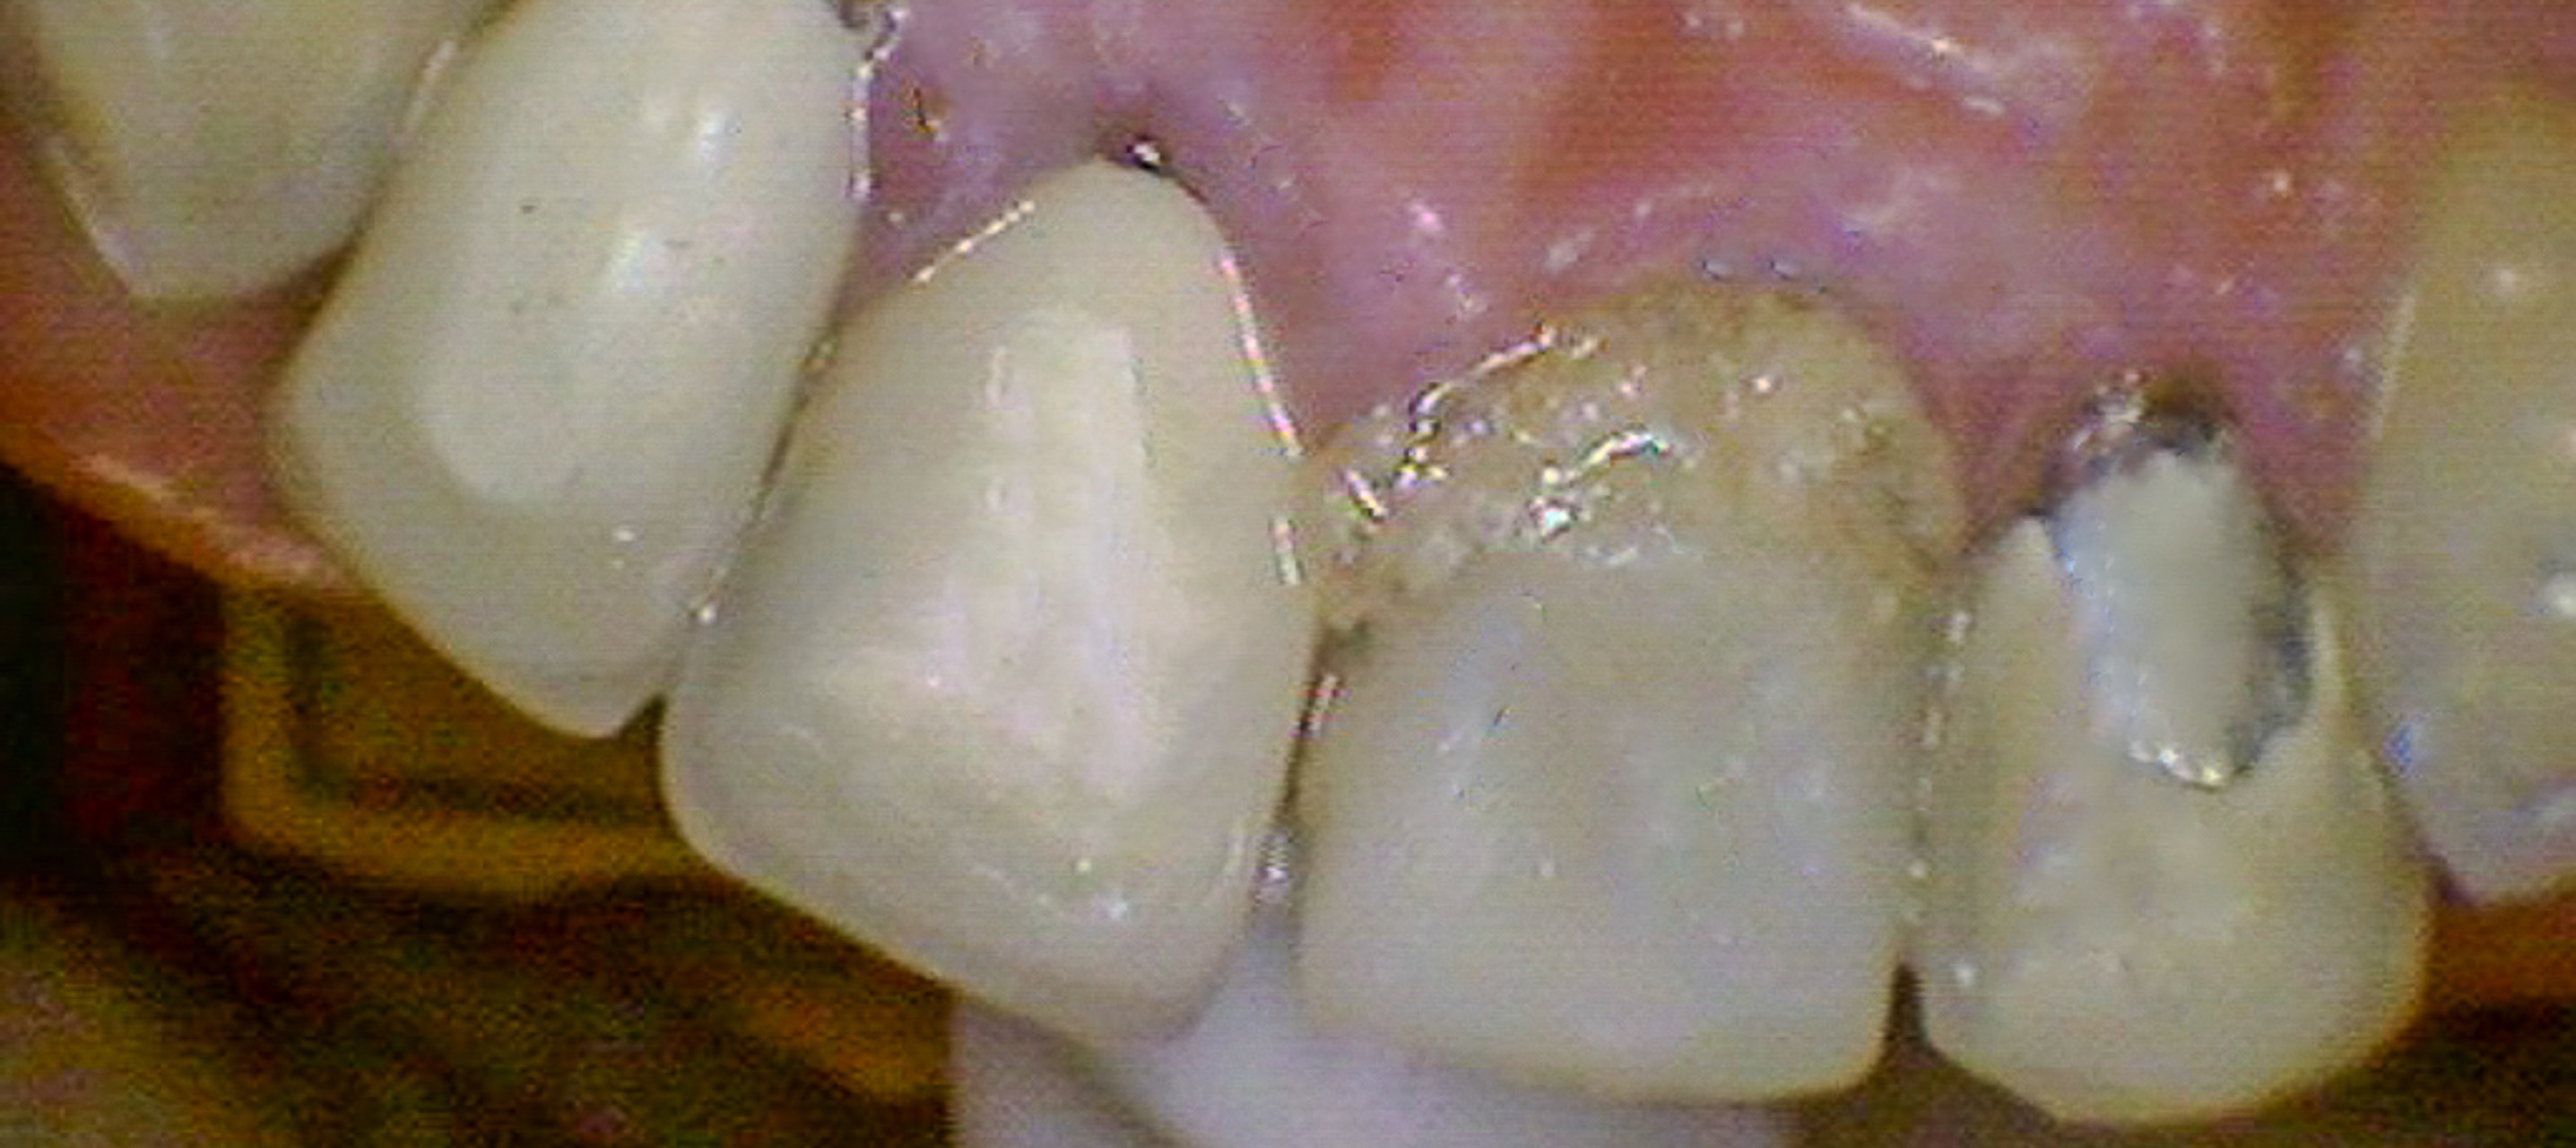

Ivan presented with unrestorable maxillary front teeth (#7–10) due to a combination of subcrestal fractures and caries. The compromised teeth were affecting both function and esthetics, with structural damage extending below the bone crest.

September 25, 2021Initial evaluation and documentation of failing maxillary front teeth with subcrestal fractures and caries involving teeth #7–10.